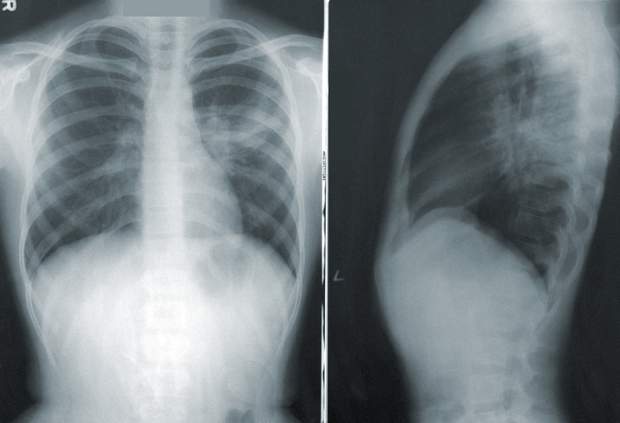

Під час гострого респіратнорного-дистрес синдрому в легенях людини починають накопичуватися інфільтрати (рідина). Внаслідок чого через деякий час легені перестають забезпечувати життєво-необхідні органи киснем. Відтак, пацієнтам із з тяжкими симптомами терапія повинна надаватися негайно. У закладі повинні бути: пульсоксиметри, робочі кисневі системи та одноразові кисневі інтерфейси.